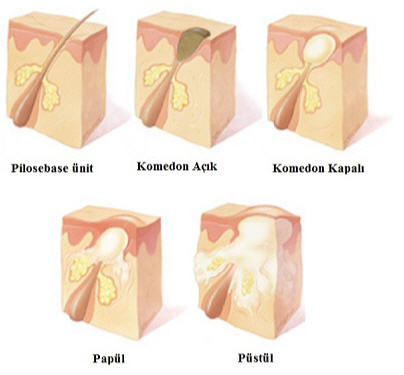

AKNE

pilosebase ünitenin kronik inflamatuar hastalığıdır.

AKNE

pilosebase ünitenin kronik inflamatuar hastalığıdır.